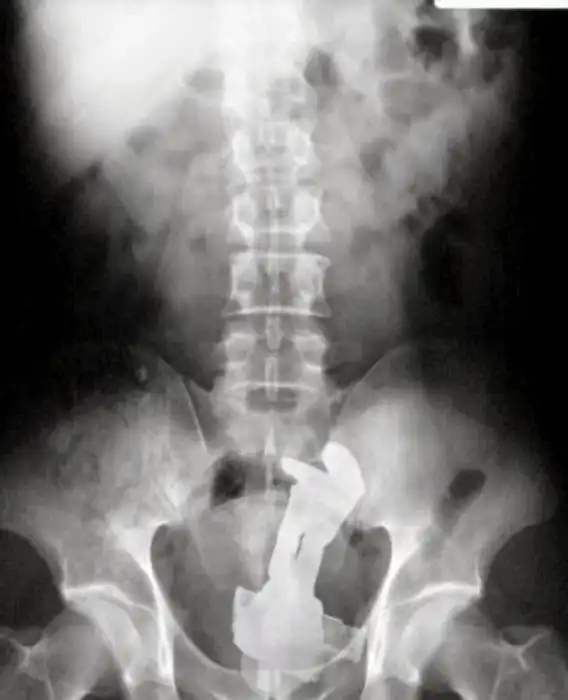

На рентгеновских снимках людей порой можно обнаружить самые необычные предметы, которые находятся в их теле.